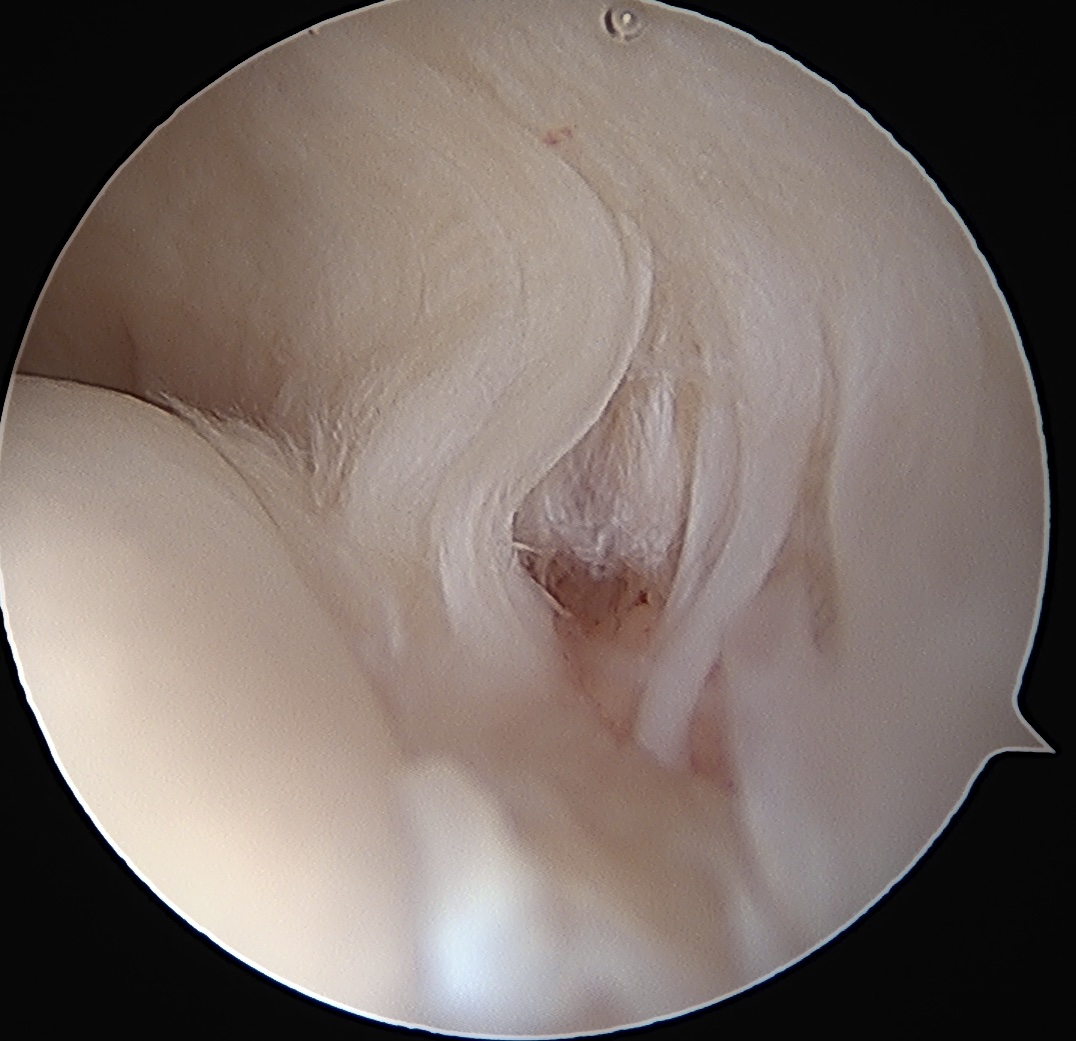

> 50% uncovering of footprint in glenohumeral joint